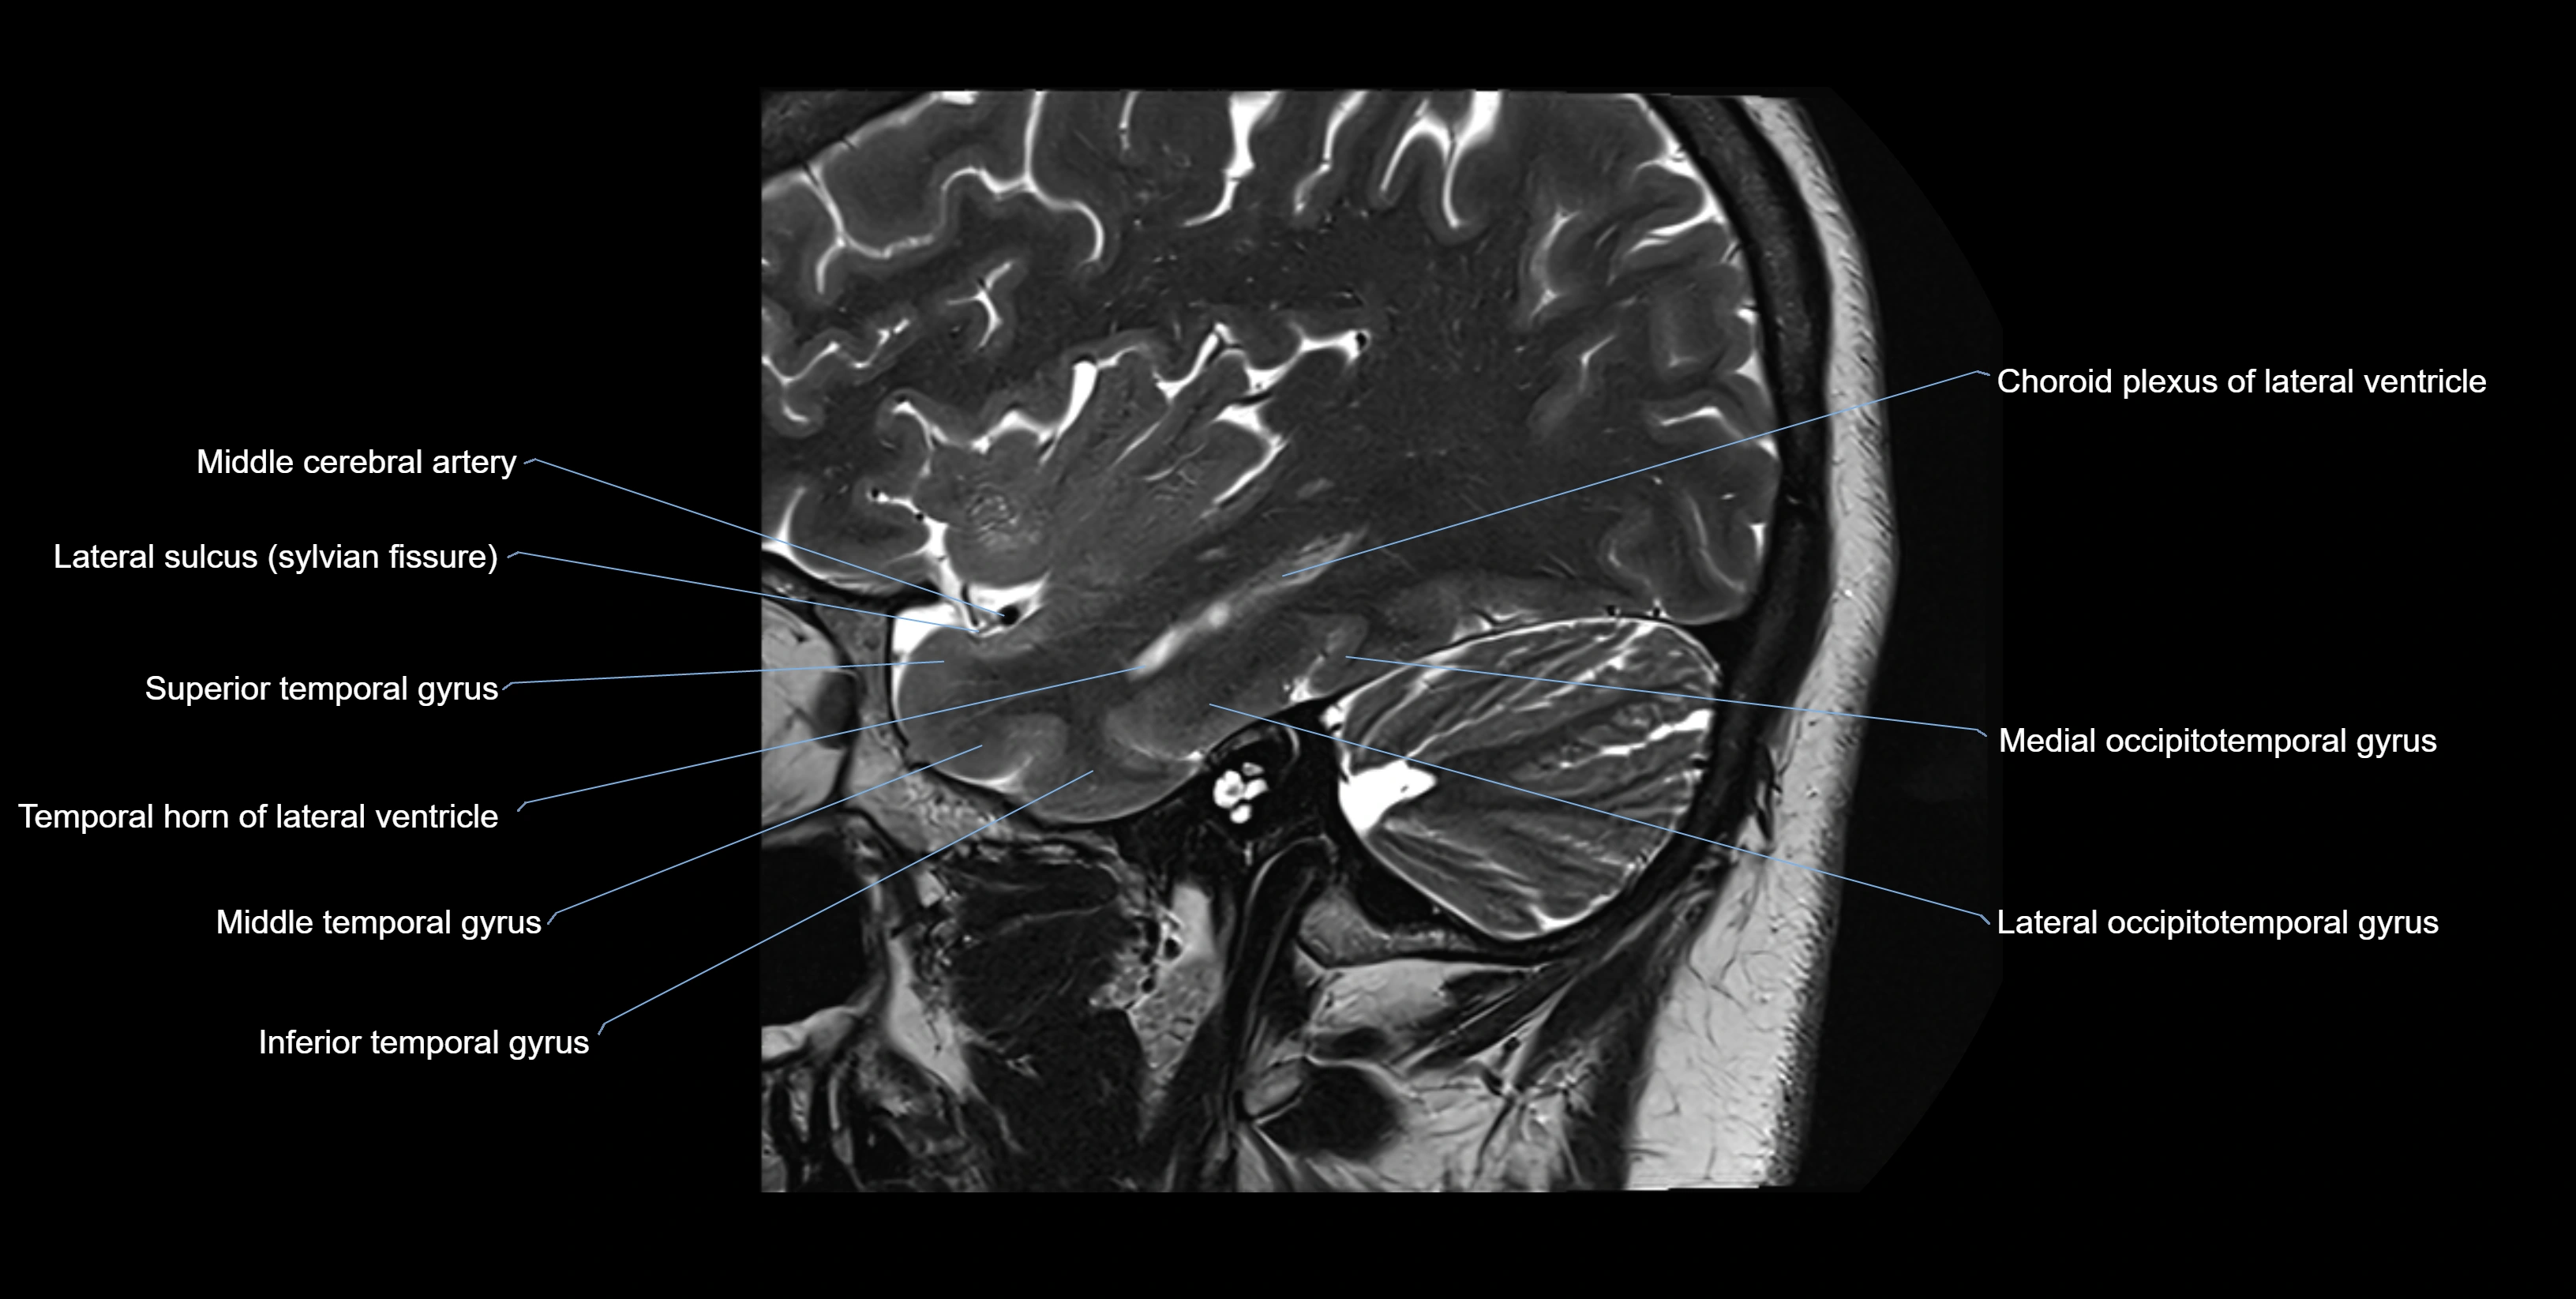

MRI Appearance

T2-weighted images:

• Alveus: Low signal line overlying brighter hippocampal gray matter.

• CSF: Bright hyperintense.